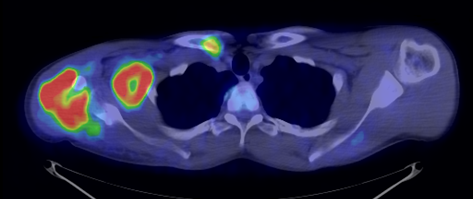

The most common clinical use of FDG-PET is in the form of whole-body scan, with oncologic indications. The majority of malignant tumors operate with higher energy consumption and show an increased glucose metabolism, consequently an increased uptake of FDG. The grade of malignancy is usually proportional to the rate of uptake. This method is useful in oncologic diagnostics, since it is capable to differentiate benign lesions from malignant ones. Whole-body PET imaging is capable to detect the primary tumor with local nodal metastases as well as distant metastatic lesions (staging) in one examination. (Figure 10.)

10. Ewing’s sarcoma in the right humerus. Staging FDG PET-CT. PET Maximum Intensity Projection (MIP) image (a), transversal (b,c) and coronal (d) plane fused PET-CT images. Multiplex metastatic process with nodal, lung and bone involvement.

In the staging of malignant diseases FDG-PET is extremely important, since it has a greater sensitivity and specificity than the morphologic imaging modalities.

This is most certainly true in case of imaging metastatic lymph nodes. Morphological imaging methods utilize size as the only reliable criteria for the differentiation of a metastatic lymph node. FDG-PET detects metabolic changes in the metastatic lesions independently of their actual size. This way, normal sized metastatic lymph nodes can be identified, as well. Larger lymph nodes that are non-metastatic in nature, but for other reasons show abnormal enlargement can also be differentiated. (Figure 11.)